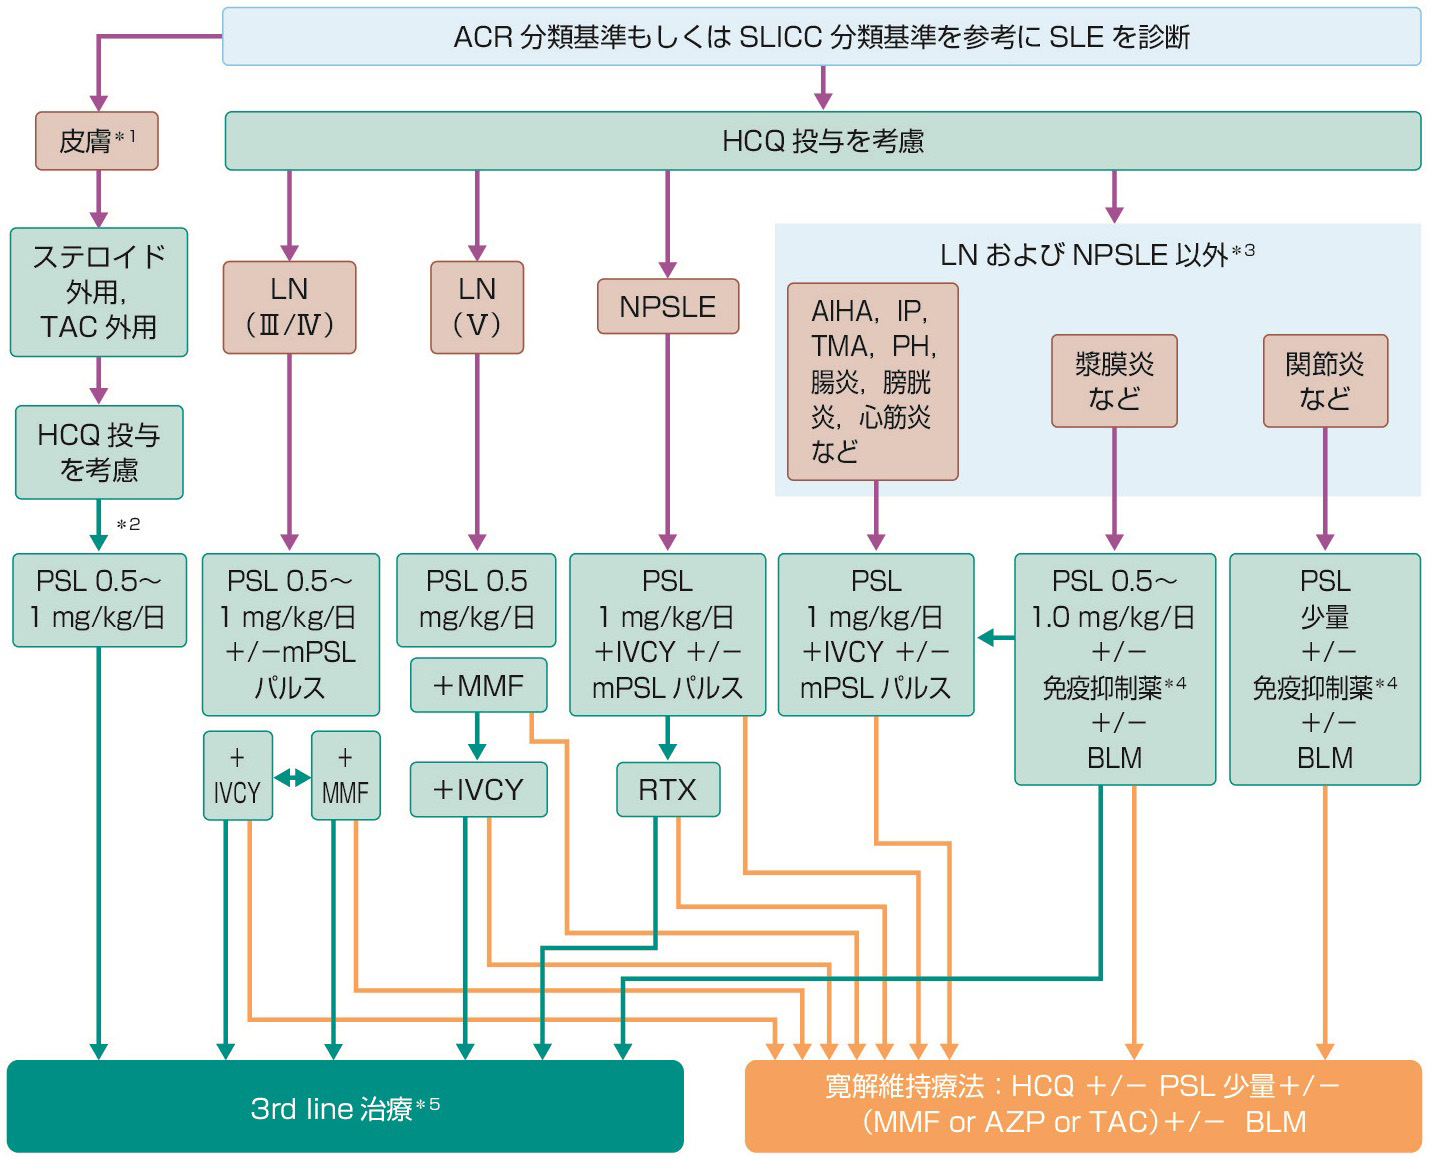

レセプター 基礎と臨床 朝倉書店 - 健康・医学 - 健康・医学。計測工学 Measurement and Instrumentation |朝倉書店。機械製図 第2版|朝倉書店。箱、傷んでいます(2〜4枚目)。傷は全体的にあります。3枚目、角のグシャッは結構グシャッです。絶対角から落としてるやろ!と声を大にして叫びたいくらいです。4枚目右の方、本を出し入れする側なのですが、変色が見られ下までずーっと続いております。反対側も半分くらいはこのような具合です。その変色部分、内側から撮ったどー(5枚目)。フヤフヤ感もあります、少しシミ的なものも。本体、角スレています(6枚目)。そして少し内側へ反っています。地、少しシミやら汚れやら(7枚目)。天も少しありますが、こちらの方が強めなのでこちらを撮りました。小口の汚れ(8枚目)。上から下までありますが、見る角度によって見えたり見えなかったりします。上の方を撮れば今の部分は綺麗に見えるという感じです。根元まで開かれています(9枚目)。大きくて厚くて重い本で古いものにはわりとありがちなのですが。これは上から下までこの状態でして、もう1ヶ所半分くらいこのような状態のページがあります。隣のページの色が移ってしまっております(10枚目)。他にもあります、これ程のものはありませんが。30年経ってますからそれなりに傷みはありますが、中身の使用感はさほど見られないように思います。スピンの紐も最初のままで一度も触っていないような感じに見えましたので。その他、写真にない箇所も写真より軽い傷みはあります、全体的に。最後になりますが。1ページずつ確認しました。吐きそうになりました。900ページ以上あるんだもの。本の重みに加え、同じ作業の繰り返しのダブルパンチで手首もやられました。両手首痛ぇー!では興味ある方はよろしくお願いいたします。。朝倉書店『内科学』(第12版)デジタル付録。大天使ミカエルオラクルカード。薬剤師 スキルアップ 8冊 服薬 皮膚 添付文書 漢方 検査 コミュ 相談 テク。新·心理診断法ロールシャッハ・テストの解説と研究。【ZERO】Structure&Function of the Body。【BLS】プロバイダーマニュアル2020&ポケットマスク。スタンダード検査血液学。【電子書籍付き第3版】グレイ解剖学【未裁断・書き込みなし】。精神医学(大月三郎)。ホスピタリストのための内科診療フローチャート第3版。理学療法ハンドブック、第3巻。【裁断済み】第3版:ホスピタリストのための内科診療フローチャート。Java silver SE 17 紫本& java se11 黒本。ライフパーパスオラクルカード 日本語版。手技療法の症状別テクニックDVD版。理学療法ハンドブック、第4巻。クエスチョン・バンク CBT 2019 vol.4 プール問題 連問編。臨床工学技士 国家試験対策。THE内科専門医問題集Ver.2 3 アレルギー・膠原病・感染症・救急・集中治療。新・口腔外科はじめましょう。看護実習 看護学生 看護過程 手順書 関連図 計画 国試 資料 アセスメント。【美品】マイナーエマージェンシー。佛教大学通信教育⭐︎免許法認定講座⭐︎特別支援学校二種5冊セット。リズブルボーの本、6冊まとめ売り。医学生・研修医のための脳神経内科。【2冊セットでお得】最新鍼灸治療学 上巻&下巻。ジェネラリストを目指す人のための画像診断パワフルガイド。小児骨折治療(裁断済)。【極美品】アレキサンダーディシプリン20の原則